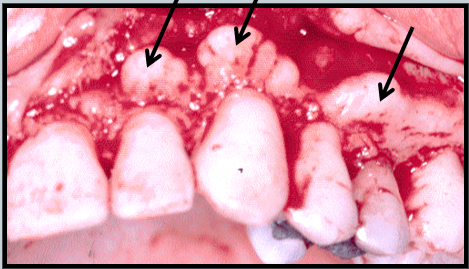

Buttressing Bone

Extra bone formation as a result of trauma

Not organized bone

Bulge or lip on facial or lingual surface

Exostoses

Bony projections in mandible or maxilla

Can affect dentures but are not symptomatic